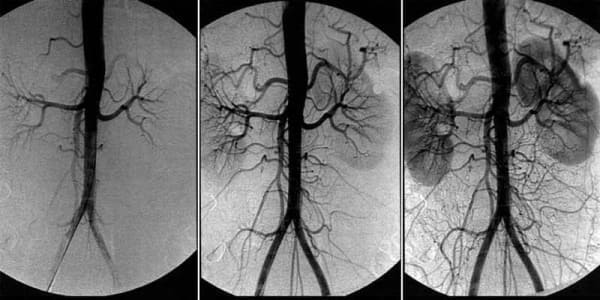

Cerebrovaskulární angiodystonie – je patologický stav, při kterém je narušen cévní tonus a normální průtok krve v mozkové tkáni. V tomto článku se dočtete o jejích příčinách, mechanismech a příznacích, kvůli kterým je čas se znepokojovat. A také o děsivých komplikacích tohoto zákeřného onemocnění a o moderním dostupném přístupu k léčbě.

"Angioedém mozku ovlivňuje výkonnost celého organismu. V důsledku nedostatečného prokrvení mozku se snižuje celková výkonnost, objevuje se slabost a začínají selhávat důležité tělesné systémy."

"Cerebrální vaskulární angiodystonie je počátečním příznakem celkového ""znečištění"" cév cholesterolem - aterosklerózy. Mozkové cévy jsou nejjemnější a nejtenčí, takže trpí jako první."

"Léčba mozkového oběhu je založena na očistě cév celého těla od nahromaděných toxinů. Cholesterolové plaky, krevní sraženiny a kalcifikace."